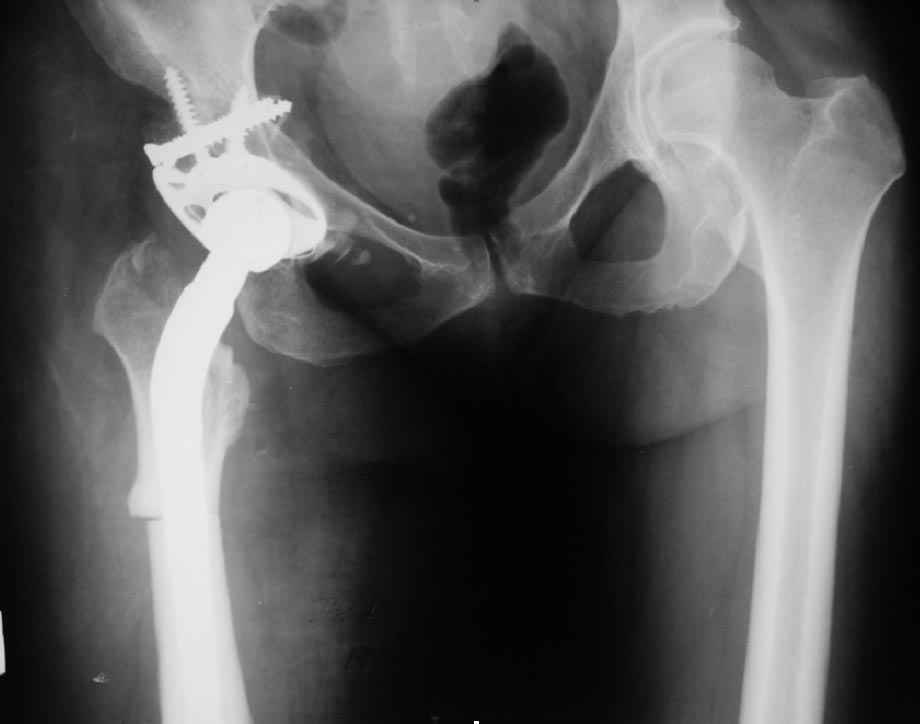

Был у нас подобный случай

Выполнена одномоментная коррекция деформации, эндопротезирование DePyu Pinnacle-AML. Пластинка с деротационной целью. При использовании ножки с прямоугольным сечением, думаю, можно и без нее.